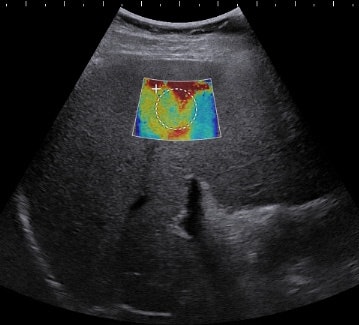

Of the 50 patients included in the study, 21 had hepatitis C. SWE was performed prior to patient biopsies using an Aixplorer system (SuperSonic Imagine) with an SC6-1 convex broadband probe. A subxyphoid approach was employed for one elastogram. With the patient in a supine or slight right anterior oblique position, two other elastograms were then acquired from the right lobe at two different craniocaudal locations. Measurements from SWE for the left lobe, right lobe (two), and biopsy location were compared with subsequent grading on pathology.

The results indicate that real-time shear-wave elastography can accurately predict significant fibrosis (stage ≥ 2) in patients with and without hepatitis C, Beland said. Also, SWE measurements taken at the biopsy site or within the same lobe in hepatitis C patients may correlate better with pathologic staging than SWE measurements taken in the contralateral lobe from the biopsy site.

At the optimized biopsy site, SWE values for detecting Metavir score F2 or greater were 1.87 m/sec (75% sensitivity and specificity) for hepatitis C patients, 2 m/sec (80% sensitivity and specificity) in nonhepatitis C patients, and 1.89 m/sec (76% sensitivity and specificity) in all patients, the researchers calculated.